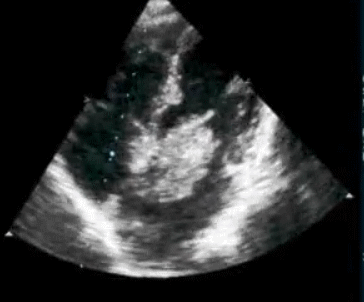

How good is Echocardiogram in diagnosing old Inferior MIs ?

Surprisingly , echocardiography do not help much either .Technically inferior transmural MI is expected to leave a residual wall motion defect. But many times it do not. Many non q inferior MI (Is there such an entity ?) do look perfectly normal by echo .

The primary reason for this is , infero-posterior surface is anatomically remote and it makes wall motion analysis difficult .Newer tissue motion analysis (Velocity vector imaging) could aid us better.

Some times a trivial or mild mitral regurgitation is the only sign of old inferior MI as the pap muscle lags behind in it’s functional recovery while free posterior wall is fully salvaged and contracting well .